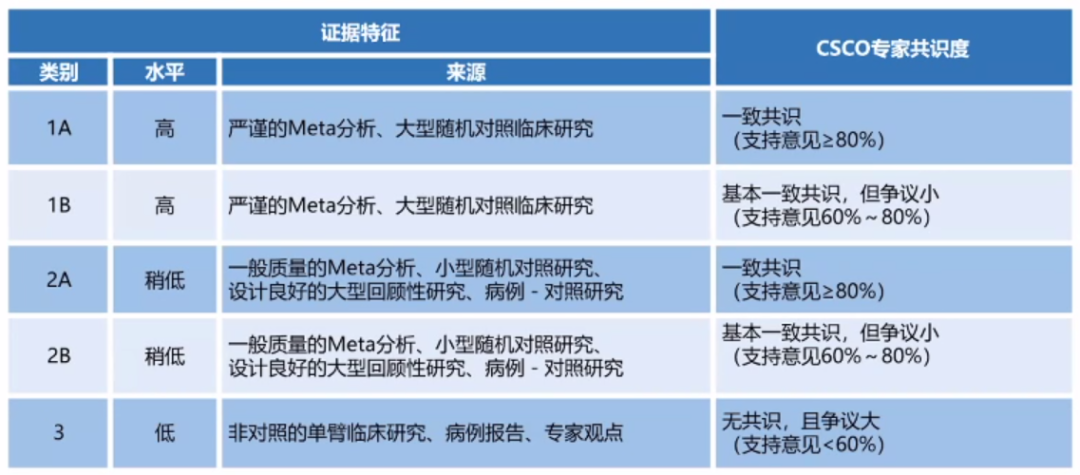

首部兼具国际水准和中国特色的前列腺癌诊疗——《CSCO前列腺癌诊疗指南》,近日重磅发布,前列腺癌领域多位专家在线解读了指南相关内容,医脉通整理了指南要点,供读者参...